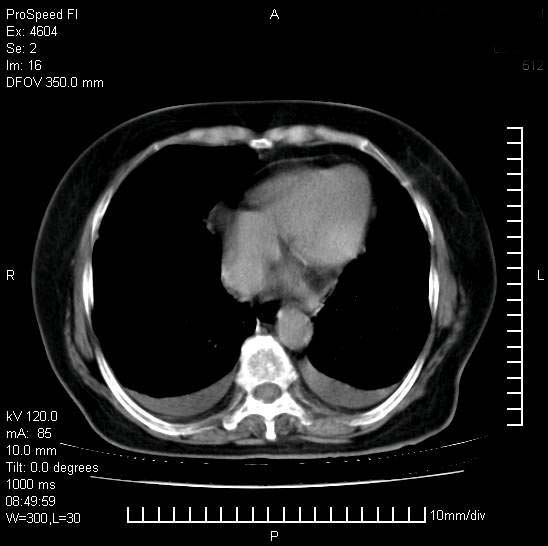

标题: CT15528:女性,79岁,近几日晚上高热,39度,仍咳少量血

十几年前曾患肺结核,一周前突咳血约100ml,中性粒细胞稍高,诊断两上肺陈旧结核,下肺炎症,给予抗炎治疗,近几日晚上高热,39度,仍咳少量血,4天前ct及今天ct上传。

[face=黑体]8月30日[/face]